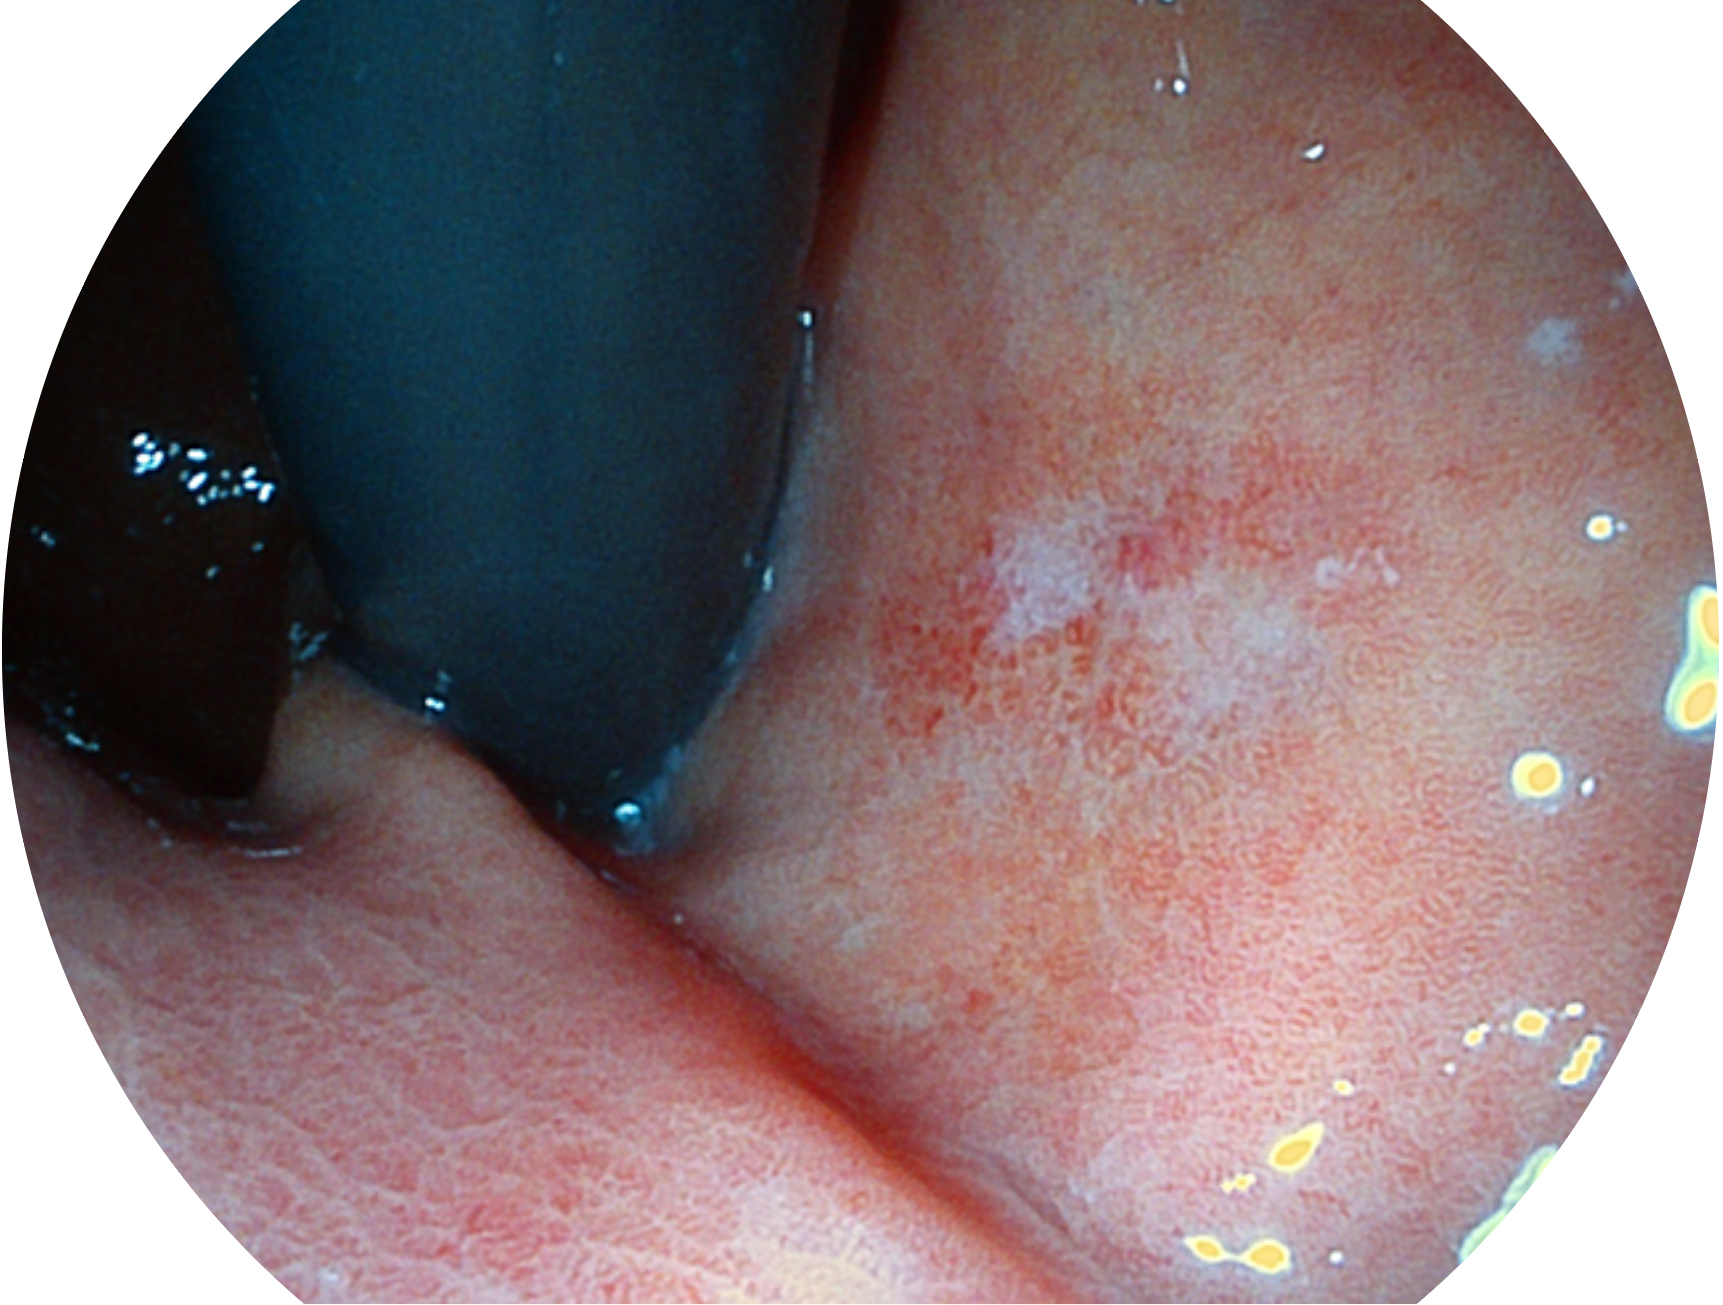

狗万官方网站新开发的内镜染色技术,主要是基于多波长LED 光源的开发,VLS-55Q 四波长LED 光源是由四个不同颜色的LED光按照相应照明模式所规定的特定发光比例进行合束后形成,合束后形成的照明光的光谱由红光、绿光、蓝光及蓝紫光这四个不同的波段范围构成。具有更高光谱自由度,通过光谱比例的控制,实现了聚谱成像技术,英文全称为“Spectral Focused Imaging, SFI”,缩写为“SFI”和光电复合染色成像技术,英文全称为“Versatile Intelligent Staining Technology, VIST”,缩写为“VIST”。